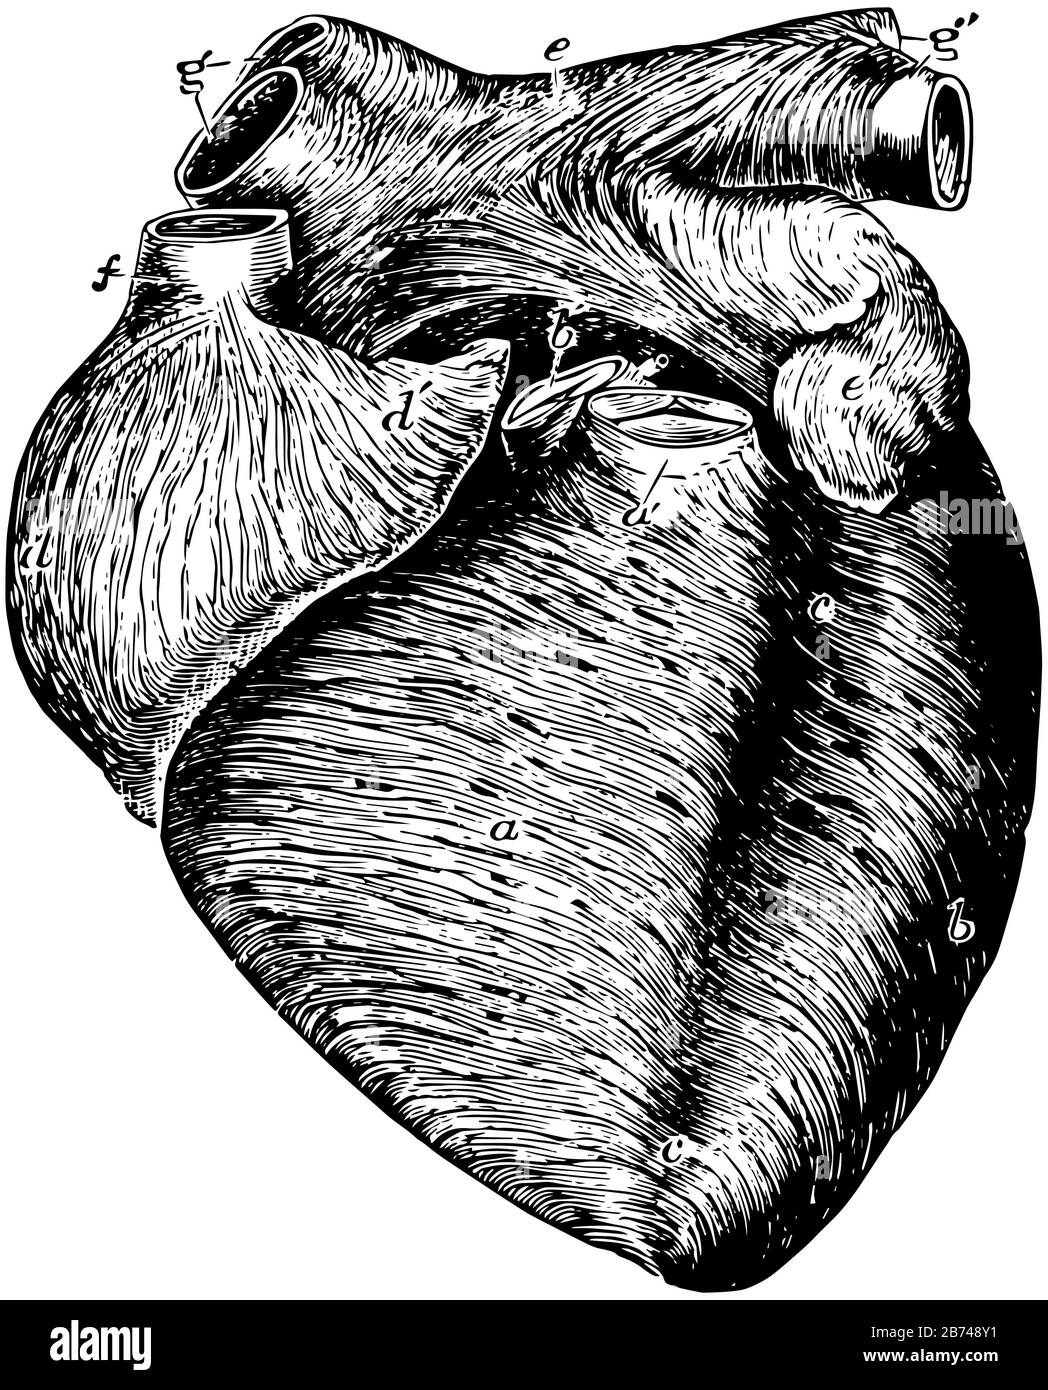

This diagram represents Anterior View of the Heart, vintage line drawing or engraving illustration. Stock Vectorhttps://www.alamy.com/image-license-details/?v=1https://www.alamy.com/this-diagram-represents-anterior-view-of-the-heart-vintage-line-drawing-or-engraving-illustration-image348604789.html

This diagram represents Anterior View of the Heart, vintage line drawing or engraving illustration. Stock Vectorhttps://www.alamy.com/image-license-details/?v=1https://www.alamy.com/this-diagram-represents-anterior-view-of-the-heart-vintage-line-drawing-or-engraving-illustration-image348604789.htmlRF2B748Y1–This diagram represents Anterior View of the Heart, vintage line drawing or engraving illustration.